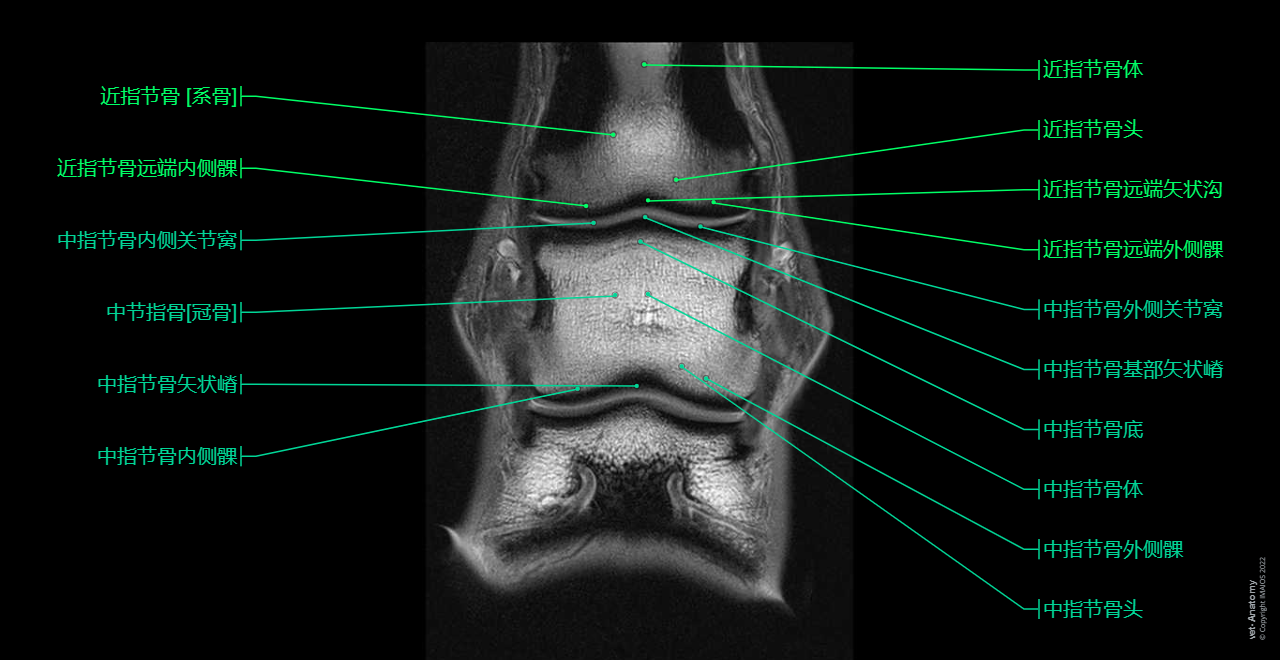

Anatomy of the equine digit (MRI): MRI - PD - Sagittal (Proximal phalanx [Long pastern bone], Middle phalanx [Short pastern bone], Distal phalanx [Ungual bone; Coffin bone; Pedal bone])

Anatomy atlas - Horse (MRI - PD - Dorsal): Thoracic limb - Forepaw